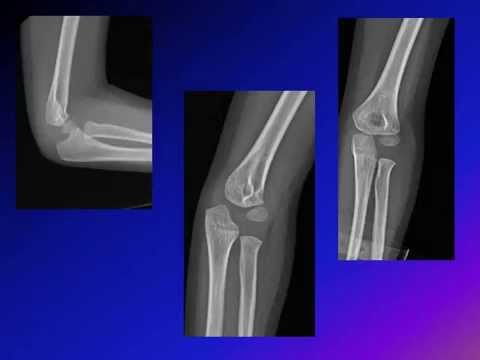

Monteggia Fracture Dislocation - Amr Abdelgaward, MD

This video describe the clinical presentation and XR findings in Monteggia fracture dislocation giving multiple examples for this injury. It will help the health care provider to avoid missing this injury in the emergency department and in the clinic as this injury is the most common missed injury in pediatric orthopedics